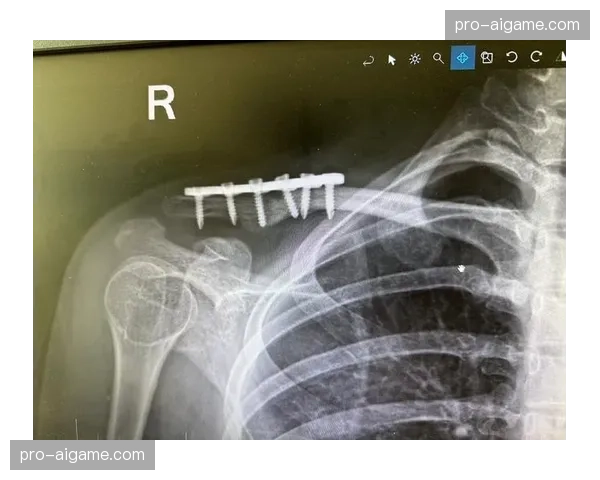

拉齐奥中场罗韦拉成功接受锁骨骨折手术,开启术后康复程序

罗韦拉在意甲联赛中的受伤事件让许多球迷感到遗憾。此次锁骨骨折手术由意大利顶级医疗团队负责,手术过程顺利,为他的康复打下了良好基础。根据医疗团队的评估,手术后的恢复期将是一个循序渐进的过程,需要严格遵循医生的建议和康复计划。